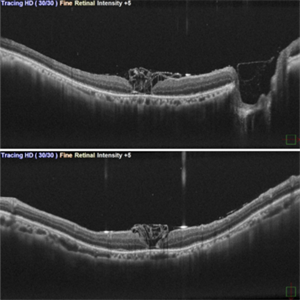

Inverted ILM Flap in RD with FTMH-First Post Op Day

Inverted ILM Flap in RD with FTMH-First Post Op Day

Oct 29 2024 by SHILPI H NARNAWARE, ICO ( Retina) , FAICO ( Vitreo-Retina)

OCT showing stuffed ILM under oil on first post op day in a case of RRD with FTMH.

Photographer: Shilpi Narnaware, Sarakshi Netralaya , Nagpur, Maharashtra , India

Imaging device: Mirante ( by Nidek)

Condition/keywords: FTMH, Inverted ILM technique, RD

Inverted ILM flap in RD with FTMH-First Post Op Day

Inverted ILM flap in RD with FTMH-First Post Op Day

Aug 23 2024 by SHILPI H NARNAWARE, ICO ( Retina) , FAICO ( Vitreo-Retina)

This is first post op day OCT of patient showing stuffed ILM in macular hole ,who underwent Vitrectomy with inverted ILM flap with silicon oil insertion in a case of RRD with FTMH.

Photographer: Shilpi Narnaware, Sarakshi Netralaya , Nagpur, Maharashtra , India

Imaging device: Mirante ( by Nidek)

Condition/keywords: FTMH, Inverted ILM technique, RD